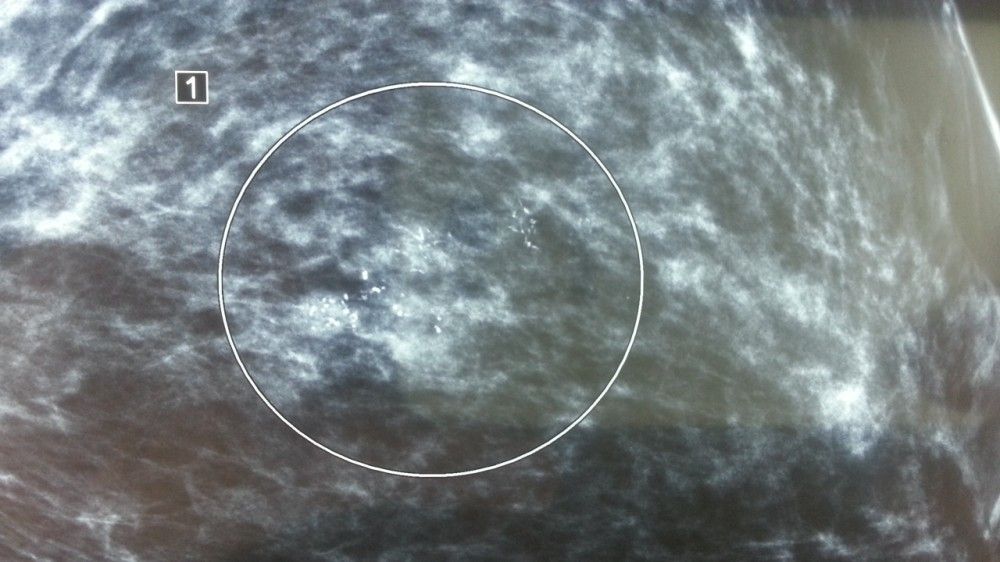

MEME KİTLELERİ VE FİBROKİSTİK HASTALIK

Bilindiği üzere meme, süt bezleri ve süt kanallarından oluşan ve asıl görevi doğum sonrası bebeği beslemek olan bir organdır. Halk ara...

MEME KANSERİNDE YANLIŞ BİLİNENLER

X;– Mememi ben kontrol ediyorum, hiç şikayetim yok, doktora gitmem gerekmez. √;– Meme kanseri ancak şikayetler başlamadan yakalandığı...